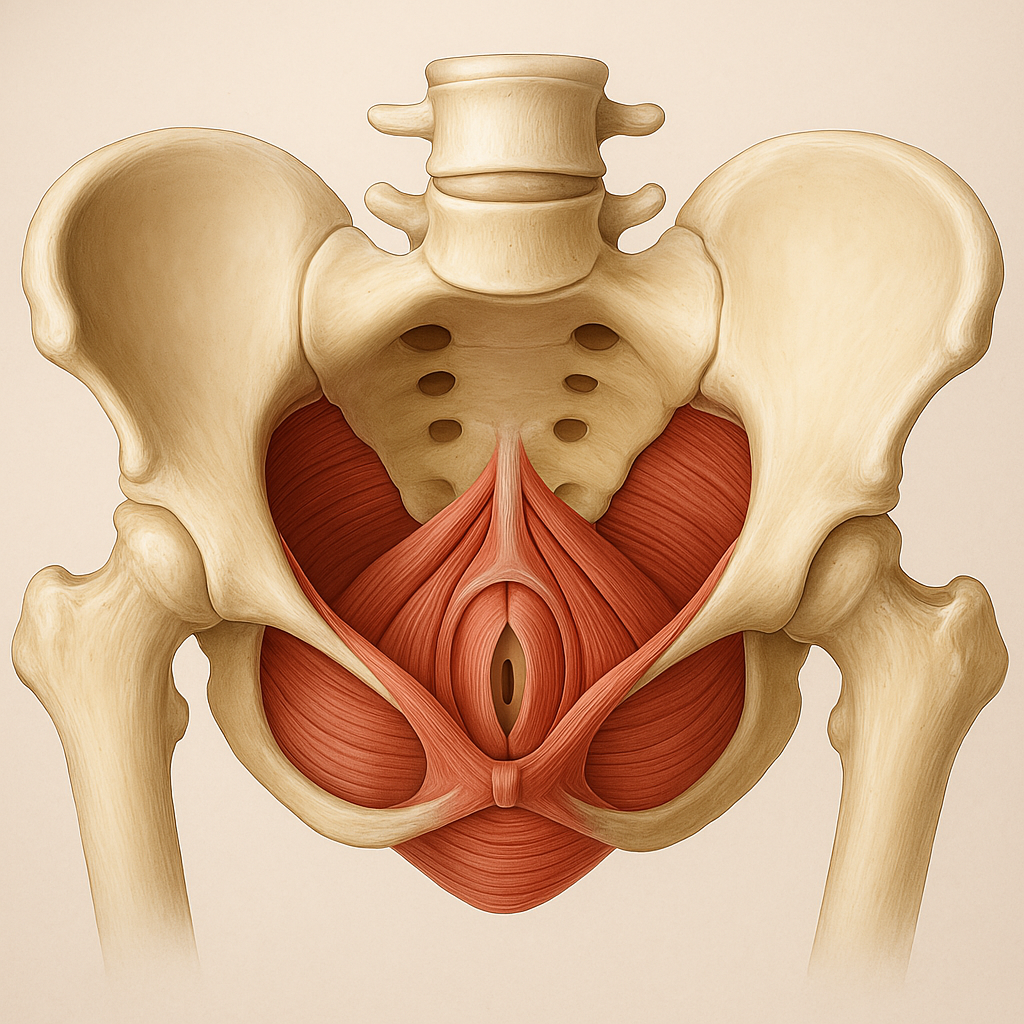

Gynekologická (také urogynekologická) fyzioterapie se zaměřuje na prevenci a léčbu funkčních poruch v oblasti pánve a pánevního dna. V praxi to znamená, že pomáhá ženám s potížemi, které se týkají nejen močového a reprodukčního systému, ale i páteře, beder, kyčlí nebo břicha. Vše je totiž propojené.

Na úvod si v klidu popovídáme. Zajímají mě nejen vaše obtíže, ale i váš cyklus, způsob práce, pohybové návyky nebo třeba to, jak sedíte v autě. Pánevní dno totiž není izolovaný prostor – reaguje na dech, držení těla i stres.

Následuje pohybové vyšetření – postoj, dech, držení těla, postavení pánve a pohyblivost. Podle potřeby provedu jemné vyšetření oblasti pánve, břicha a případně i vnitřní vyšetření přes pochvu nebo konečník – ale jen pokud s tím budete souhlasit a pokud je to nutné pro stanovení dalšího postupu. Vždy vše předem vysvětlím a je možné kdykoliv říct „ne“.